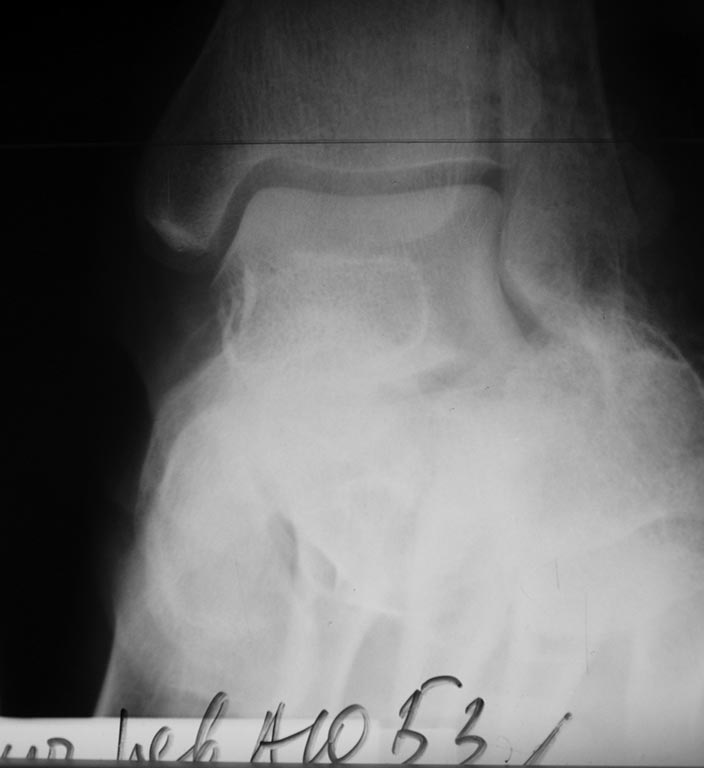

Пациент 53 года поступил 23.04.17 после падения со второго этажа. Ds:

Сочетанная травма ЗЧМТ. СГМ. О. перелом 3А (по Gustilo-Andersen) левой

пяточной кости.Рана около 10 см по внутренней поверхности г/стопного

сустава с переходом на пяточную область. Края раны не осаднены,

жизнеспособны.

Выполнена ПХО, устранение грубого смещения, фиксация спицами,

гипсовая иммобилизация. На 26.04.17 рана без воспаления, отделяемое

минимально геморрагическое.

После снятия швов и гладкого заживления раны (думаю,что так будет)

планирую реостеосинтез из наружного доступа ниже лодыжки с элевацией

задней фасетки, анатомичной репозицией бугра и костной аутопластикой,

фиксация спицами.